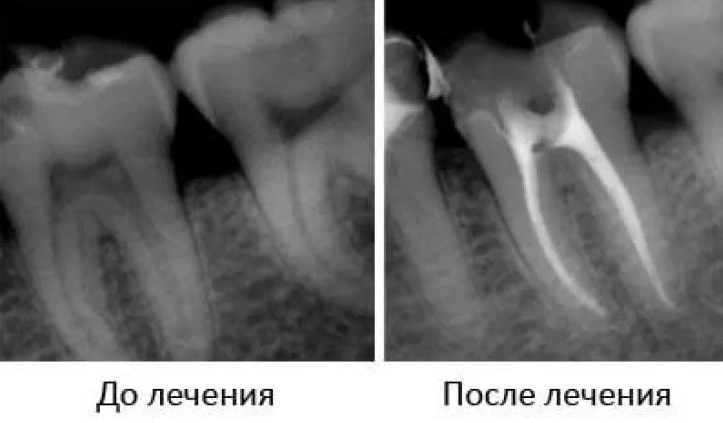

Наличие рентгеновских или цифровых снимков предоставляет возможность контролировать состояние депульпированного зуба и выявлять пустоты в корневых каналах. Рентгеновское изображение до начала лечения помогает определить форму и количество корней в молярах. Обычно боковые моляры обладают разветвлёнными и глубокими корнями. Таким образом, рентген зуба проводится дважды в процессе лечения – в начале и после завершения пломбировки каналов.

На этих изображениях — рентгеновские снимки корней. Пломбировочный материал в зубе и корнях отображается сплошным белым цветом.